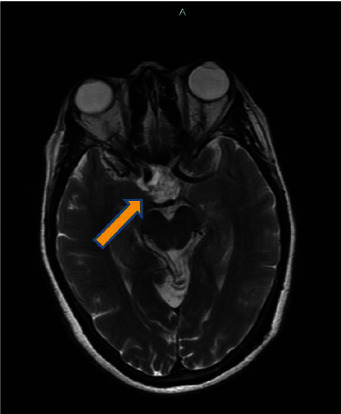

In this report, we present the case of a 71-year-old African-American woman experiencing 2 months of intermittent headaches and episodes of blurred vision. Despite a comprehensive medical history that revealed chronic conditions and previous unrelated surgeries, the initial evaluation appeared to be unremarkable. Following the discovery of a mass on an imaging and a subsequent biopsy, the diagnosis of craniopharyngioma (WHO grade I) was confirmed. However, a brain mass was identified after additional ophthalmologic examination and MRI. This case explores the significance of recognizing atypical presentations of a brain injury that required a specific approach for diagnosis, surgical intervention and treatment, and postoperative care. This case contributes to the constantly evolving understanding of atypical manifestations of tumor characteristics and their complexities, along with the need to develop appropriate patient management strategies and provide optimal outcomes.